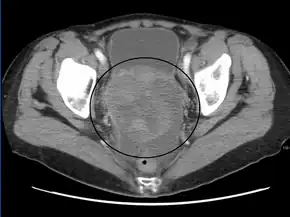

A very large ovarian cancer as seen on CT

Diagnosis of ovarian cancer starts with a physical examination (including a pelvic examination), a blood test (for CA-125 and sometimes other markers), and transvaginal ultrasound.[26][56] Sometimes a rectovaginal examination is used to help plan a surgery.[29] The diagnosis must be confirmed with surgery to inspect the abdominal cavity, take biopsies (tissue samples for microscopic analysis), and look for cancer cells in the abdominal fluid. This helps to determine if an ovarian mass is benign or malignant.[26]

CT scanning is preferred to assess the extent of the tumor in the abdominopelvic cavity, though magnetic resonance imaging can also be used.[28] CT scanning can also be useful for finding omental caking or differentiating fluid from solid tumor in the abdomen, especially in low malignant potential tumors. However, it may not detect smaller tumors. Sometimes, a chest x-ray is used to detect metastases in the chest or pleural effusion. Another test for metastatic disease, though it is infrequently used, is a barium enema, which can show if the rectosigmoid colon is involved in the disease. Positron emission tomography, bone scans, and paracentesis are of limited use; in fact, paracentesis can cause metastases to form at the needle insertion site and may not provide useful results.[29] However, paracentesis can be used in cases where there is no pelvic mass and ascites is still present.[29] A physician suspecting ovarian cancer may also perform mammography or an endometrial biopsy (in the case of abnormal bleeding) to assess the possibility of breast malignancies and endometrial malignancy, respectively. Vaginal ultrasonography is often the first-line imaging study performed when an adnexal mass is found. Several characteristics of an adnexal mass indicate ovarian malignancy; they usually are solid, irregular, multilocular, and/or large; and they typically have papillary features, central vessels, and/or irregular internal septations.[31] However, SCST has no definitive characteristics on radiographic study.[33]